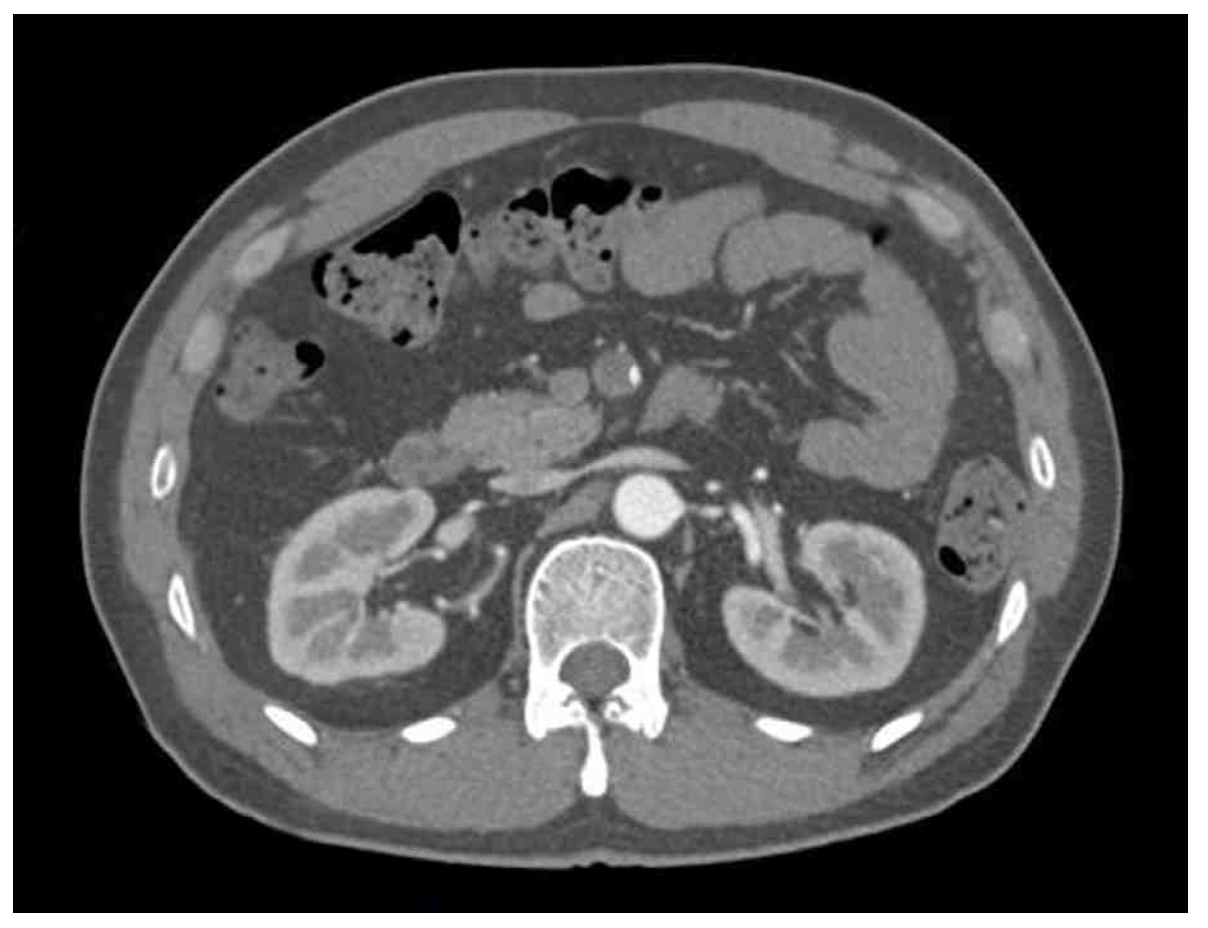

CT: Superior mesenteric artery obstruction

급성 복통 및 혈변을 호소하는 Afib환자의 복부CT상 상장간동맥의 폐쇄가 확인되므로 상장간동맥색전(SMA embolism)으로 진단한다.

• 추가적으로 시행한 복부 CT상에서 상장간동맥(SMA)의 폐쇄가 관찰된다.

• 급성적인 복통 및 혈변을 호소하는 AF 환자에게서 복부 CT상 상장간동맥의 폐쇄가 확인되므로 상장간동맥색전(SMA embolism)으로 진단한다.